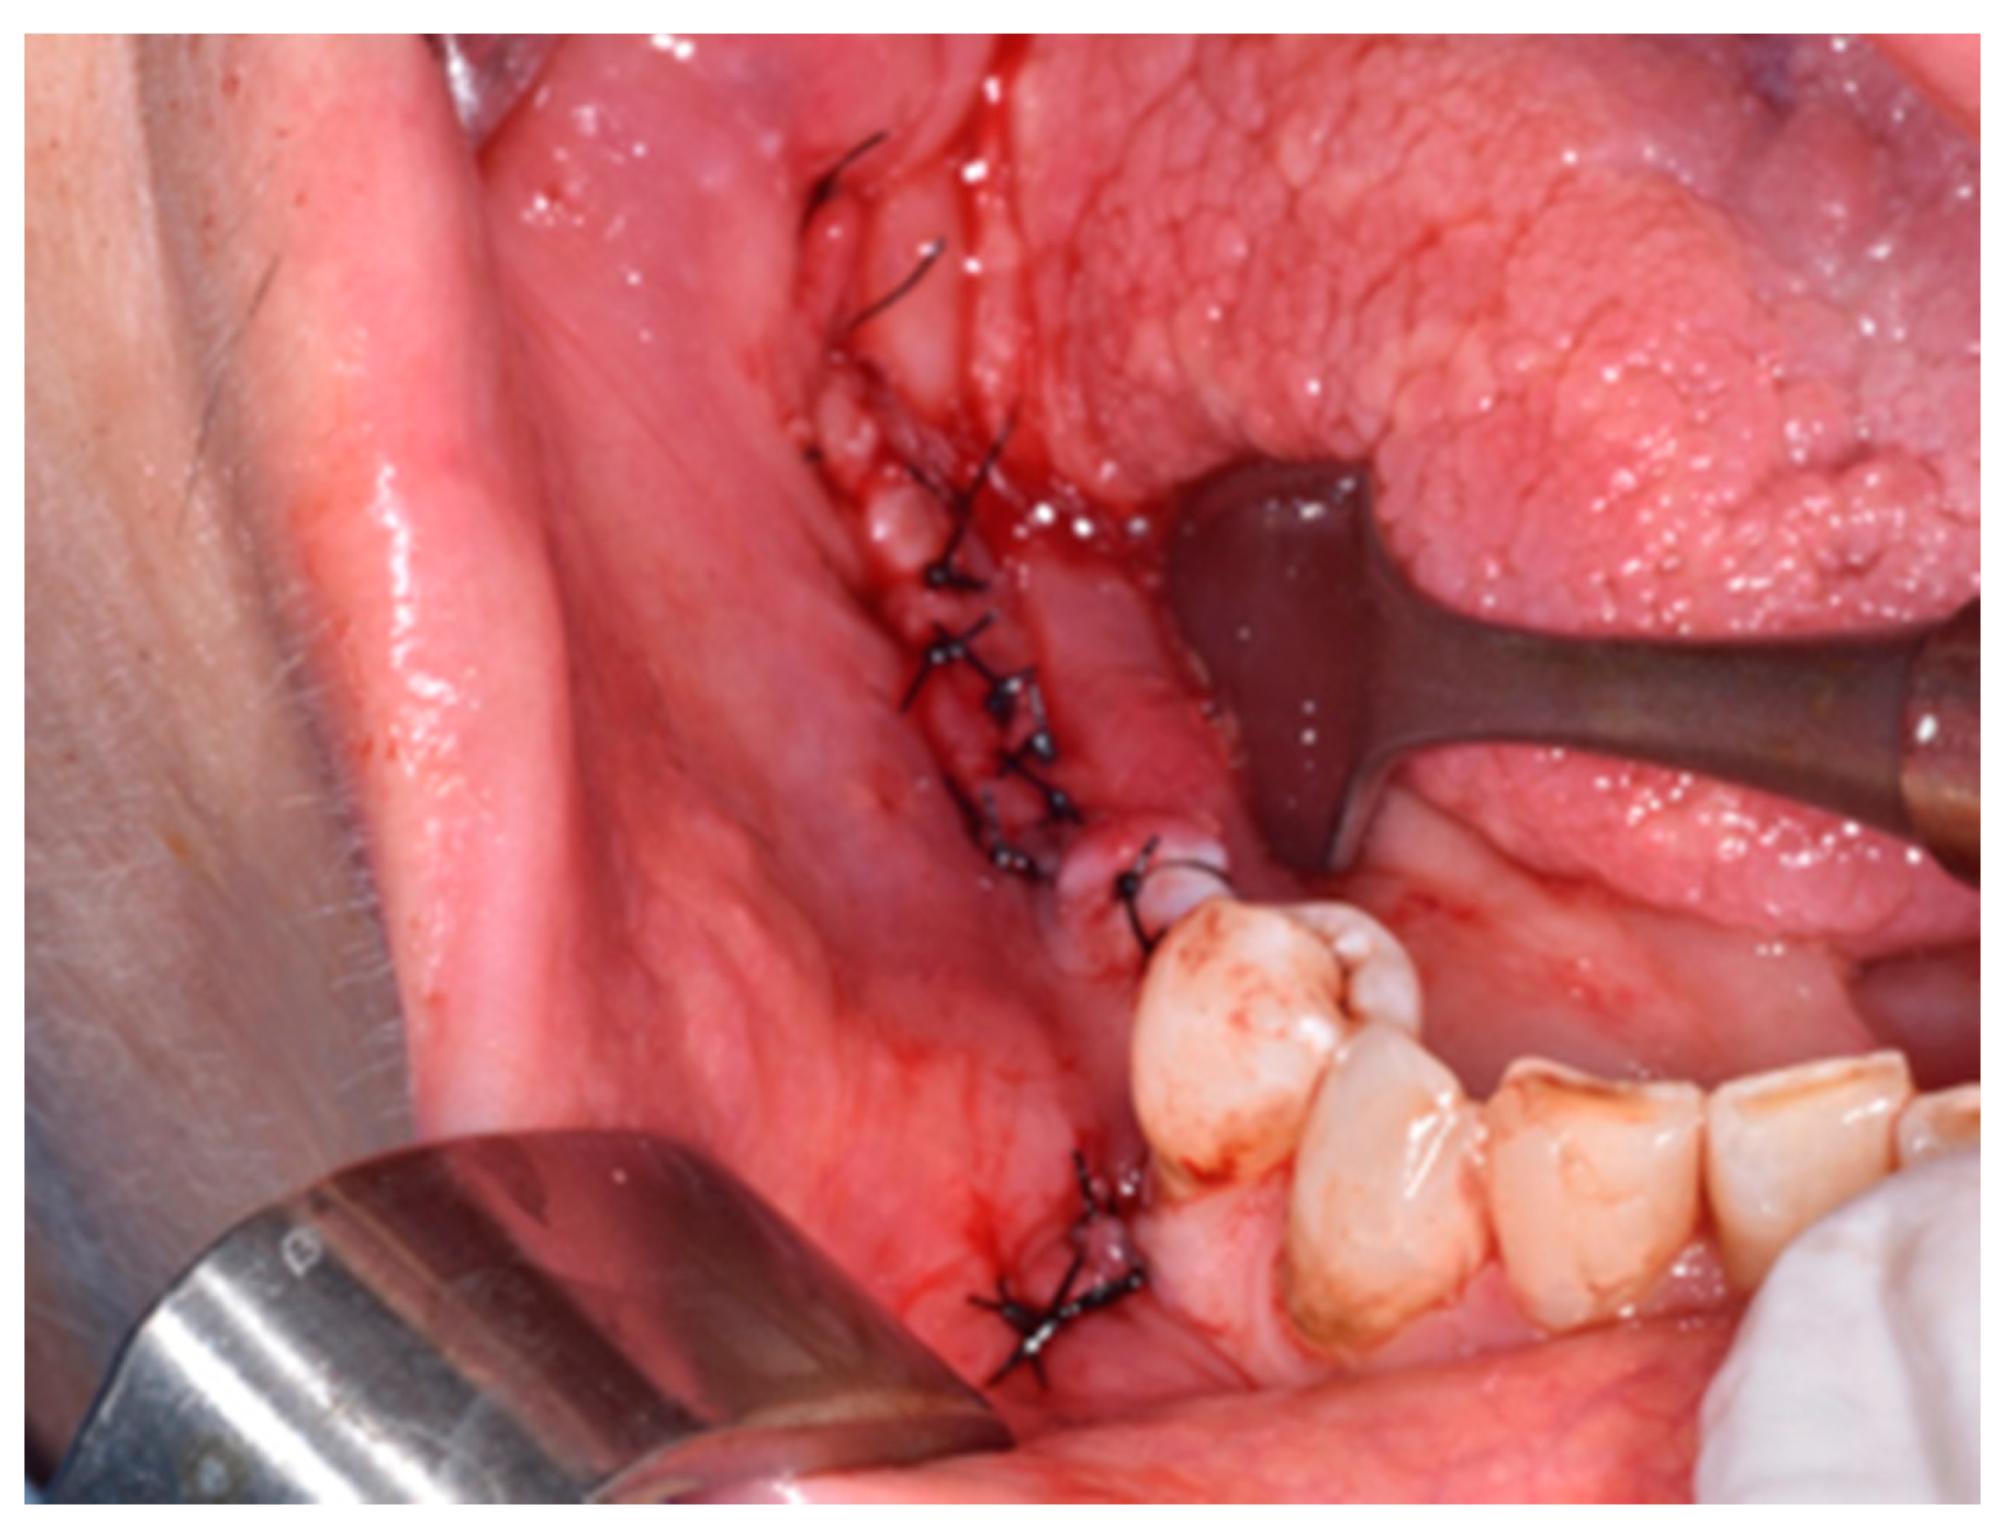

2. Materials and Methods

3. Results

4. Discussion